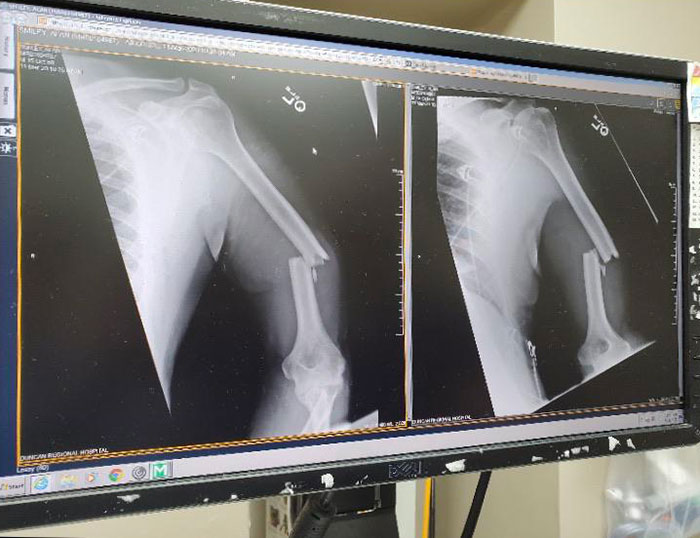

My (Nearly 60-Years-Old) Father's Arm After Being Thwomped By A Cow This Morning

Went Through 21 Years Thinking I Never Broke A Bone Until An X-Ray For A Shoulder Problem Revealed This Atrocity, It Broke And Healed Without Me Knowing, Was Nice Knowing You